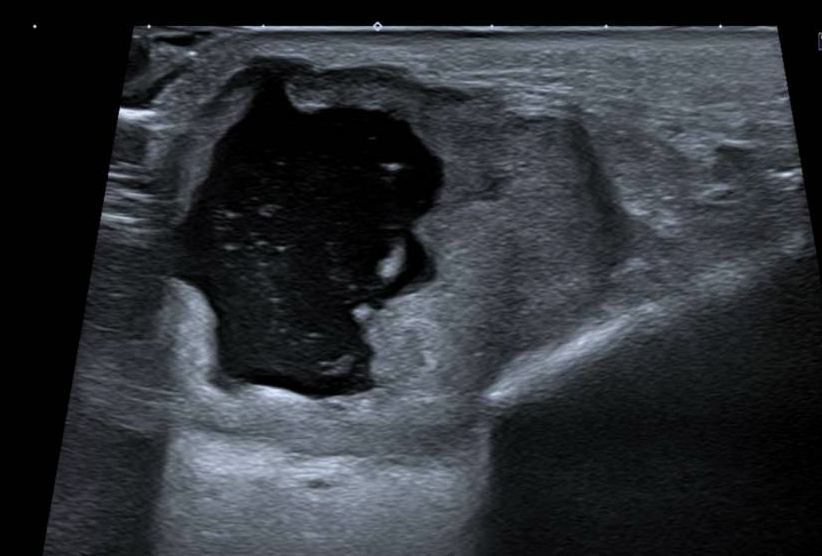

Pruebas complementarias

Tras valoración por ORL, tres meses después, en ecografía de parótida derecha: nódulo sólido-quístico intraparotideo, con halo hiperecoico periférico, circunscrito y con escasa vascularización intranodular. Adenopatía local atípica que amplia el diagnóstico diferencial sin poder descartar malignidad primaria o metastásica.